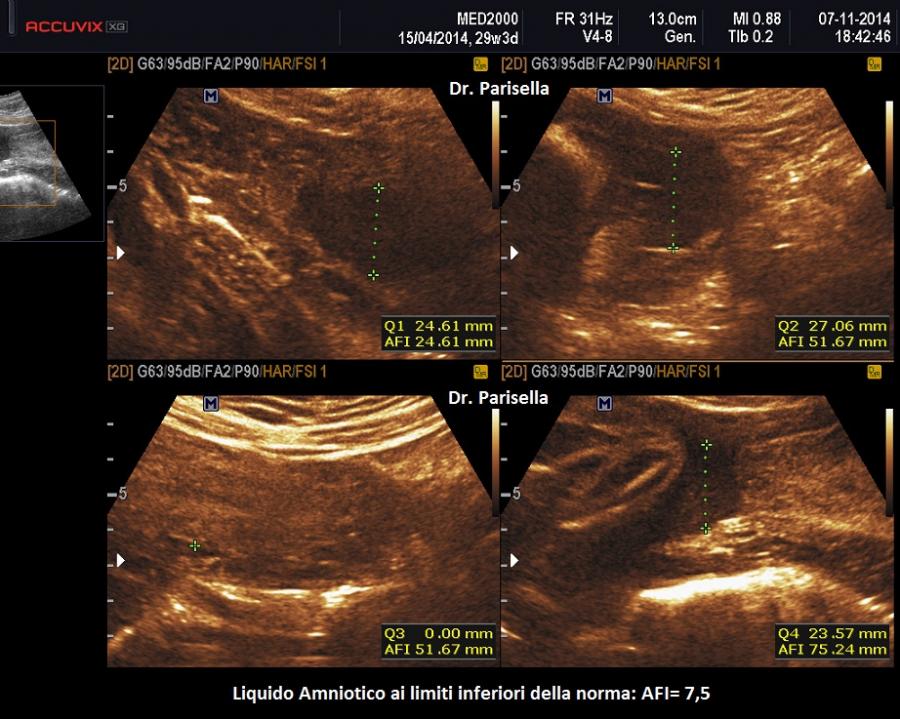

La quantità di liquido amniotico è indicativa del benessere fetale e le sue alterazioni possono essere la manifestazione di processi patologici che interessano sia la madre che il feto. La valutazione dell'AFV è pertanto una componente essenziale dell'esame ecografico in gravidanza (Magann EF, 2017). I due metodi di misurazione ecografica del liquido amniotico sono la misurazione dell'indice di liquido amniotico AFI (amniotic fluid index) (Rutherford SE, 1987- Moore TR, 1990) e la misurazione della tasca massima (T max) (Manning FA, 1980-Chamberlain PR, 1984). L'AFI si ottiene col metodo dei 4 quadranti: si divide la cavità amniotica in 4 quadranti tracciando una linea mediana verticale ed una linea trasversale a metà strada tra sinfisi pubica e fondo uterino; si individua la tasca di liquido più grande in ciascun quadrante, escludendo i punti dove sono presenti le parti fetali e si effettua la misurazione verticale delle tasche massime in centimetri; la somma delle quattro misurazioni rappresenta l'AFI. Il valore normale di riferimento dell'AFI è: 5-25 cm. Al disotto dei 5 cm. si parla di oligoidramnios, al disopra dei 25 cm. si parla di polidramnios.

Il metodo che sembra la scelta migliore (La singola tasca più profonda nella valutazione del volume del liquido amniotico per la sorveglianza fetale sembra una scelta migliore poiché l’uso dell’AFI aumenta il tasso di diagnosi di oligoidramnios e il tasso di induzione senza miglioramento degli esiti peripartum.Nabhan AF, 2008-2009) è quello di considerare la misurazione verticale della tasca massima nel metodo dei 4 quadranti. I valori di riferimento della Tmax sono 2-8 cm.; se la Tmax è inferiore a 2 si parla di oligoidramnios; se la Tmax è superiore a 8 si parla di polidramnios distinto in lieve lieve (8-11 cm), moderato (12-15 cm) e severo (≥16 cm).

Nell'oligoidramnios la misurazione della tasca massima di liquido amniotico è inferiore a 2 cm. e l'indice di liquido amniotico è inferiore a 5 cm. La tasca singola più profonda è il metodo migliore per la valutazione dell'oligoidramnios e per la valutazione delle gravidanze gemellari. Un liquido amniotico ai limiti inferiori della norma (AFI compreso tra 5 e 8) si può associare a FGR/IUGR (ritardo di crescita intrauterino) o può essere fisiologico a fine gravidanza. Sono essenzialmente tre le cause principali di oligoidramnios prima della 24° settimana (Fetal Medicine Foundation FMF): Anomalie delle vie urinarie, Rottura prematura delle membrane (PROM), Insufficienza uteroplacentare (FGR/IUGR); a queste bisogna aggiungere l'esposizione materna ad alcuni farmaci.